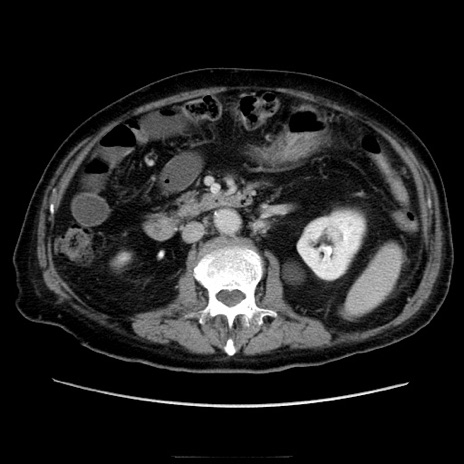

症例21(横断像)

【症例】70歳代男性

【主訴】腹痛

【現病歴】肝硬変・肝細胞癌にてかかりつけの方。約9時間前に食後より腹痛出現。症状が徐々に増悪し、嘔吐出現したため来院。

【既往歴】肝硬変、肝細胞癌(RFA、TACE後)

【身体所見】意識清明、表情苦悶様、BT 36℃、BP 129/78mmHg、P 88bpm、SpO2 97%(RA)、右上腹部から心窩部にかけて圧痛あり、反跳痛なし、筋性防御あり。

【データ】WBC 5800、CRP 0.16